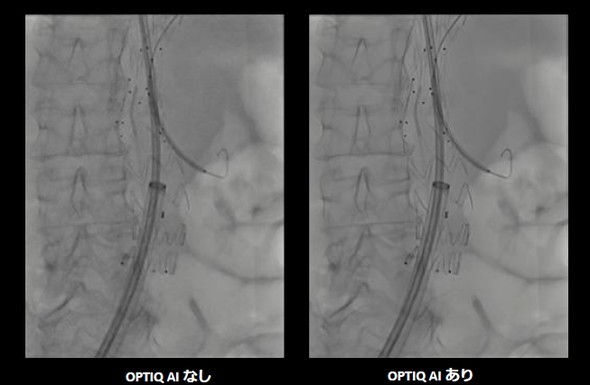

キャプション AIを用いた画像処理技術「OPTIQ AI」の有無別画像[クリックで拡大] 出所:シーメンスヘルスケア

ARTIS pheno.visionは、ハイブリッド手術室向けのX線透視、撮影装置「ARTIS pheno」に、AI画像処理技術の「OPTIQ AI」を搭載したモデルだ。画像生成プロセスにおいてノイズを大幅に抑制し、高精細かつ高コントラストな画像を可能にした。

コントラストノイズ比(CNR)に基づく画像処理により、患者の体格差やCアームの角度、システム条件などに左右されず、安定した画像を提供できる。AIを活用した高度なアルゴリズムは、信号強度を維持したまま量子ノイズや電子ノイズをリアルタイムで除去する。X線散乱などのノイズが抑制されるため、微細な血管や細径化が進むカテーテル、ガイドワイヤなどをクリアに描出可能だ。